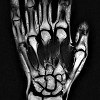

МРТ кисти

Магнитно-резонансная щетка. Современная диагностическая процедура, позволяющая получать послойные изображения костей и мягких тканей кисти, измеряя реакцию ядер водорода, возбуждаемых определенной комбинацией радиоволн в интенсивном магнитном поле. Он используется на заключительных этапах диагностического поиска с сомнительными или неоднозначными результатами рентгенологического исследования и компьютерной томографии. Показывает состояние костей и суставов пальцев, пястных костей и костей запястья, а также мышц, сухожилий и кровеносных сосудов кисти. Он используется в процессе диагностики артрита, артрита, переломов, вывихов, разрывов связок, травматических повреждений мышц, аномалий развития, опухолей, остеомиелита, теносиновита, тромбоза ладоней, туннельного синдрома и контрактуры Дюпюитрена.